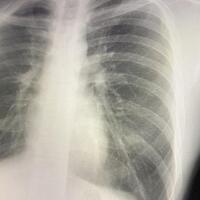

アルファ株やデルタ株といった変異ウイルスが猛威をふるっていた時期とは異なり、現在流行している「JN.1」はオミクロン株の一種なので、基本的には軽症で済むことが多いです。しかし、最近増えているのが「新型